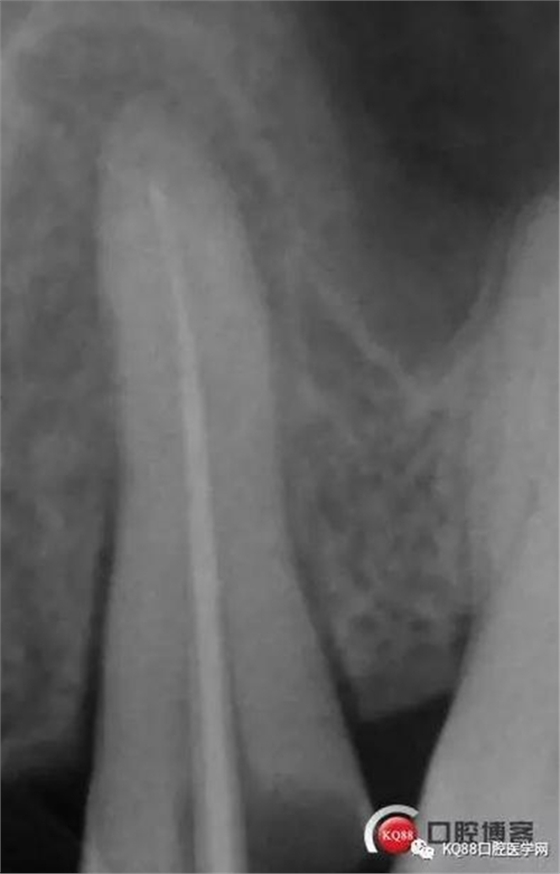

當(dāng)我第一次完成操作后,再次拍了一個插針片,發(fā)現(xiàn),距離根尖孔有1.5mm,書上說的是2mm安全區(qū),可能如果隨意點(diǎn),就直接充填了,我想說明的是,我們做根管,千萬不要馬虎,不要湊合,一定嚴(yán)謹(jǐn)?shù)膽B(tài)度,于是我重新再回到C銼,再開始耐心的預(yù)備,完成之后,再拍攝了插針片。

此次明顯可以看見根尖分開了兩個根尖孔,根管治療永遠(yuǎn)就只是那一點(diǎn),如果都只是隨便做一下,我相信,沒有復(fù)雜的牙齒,根管治療都會很簡單,態(tài)度決定一切,我不敢說我做的會很好,但是我會靜下心來,慢慢操作,這樣才能做得對的起自己和患者。于是根充完成,再次拍攝。